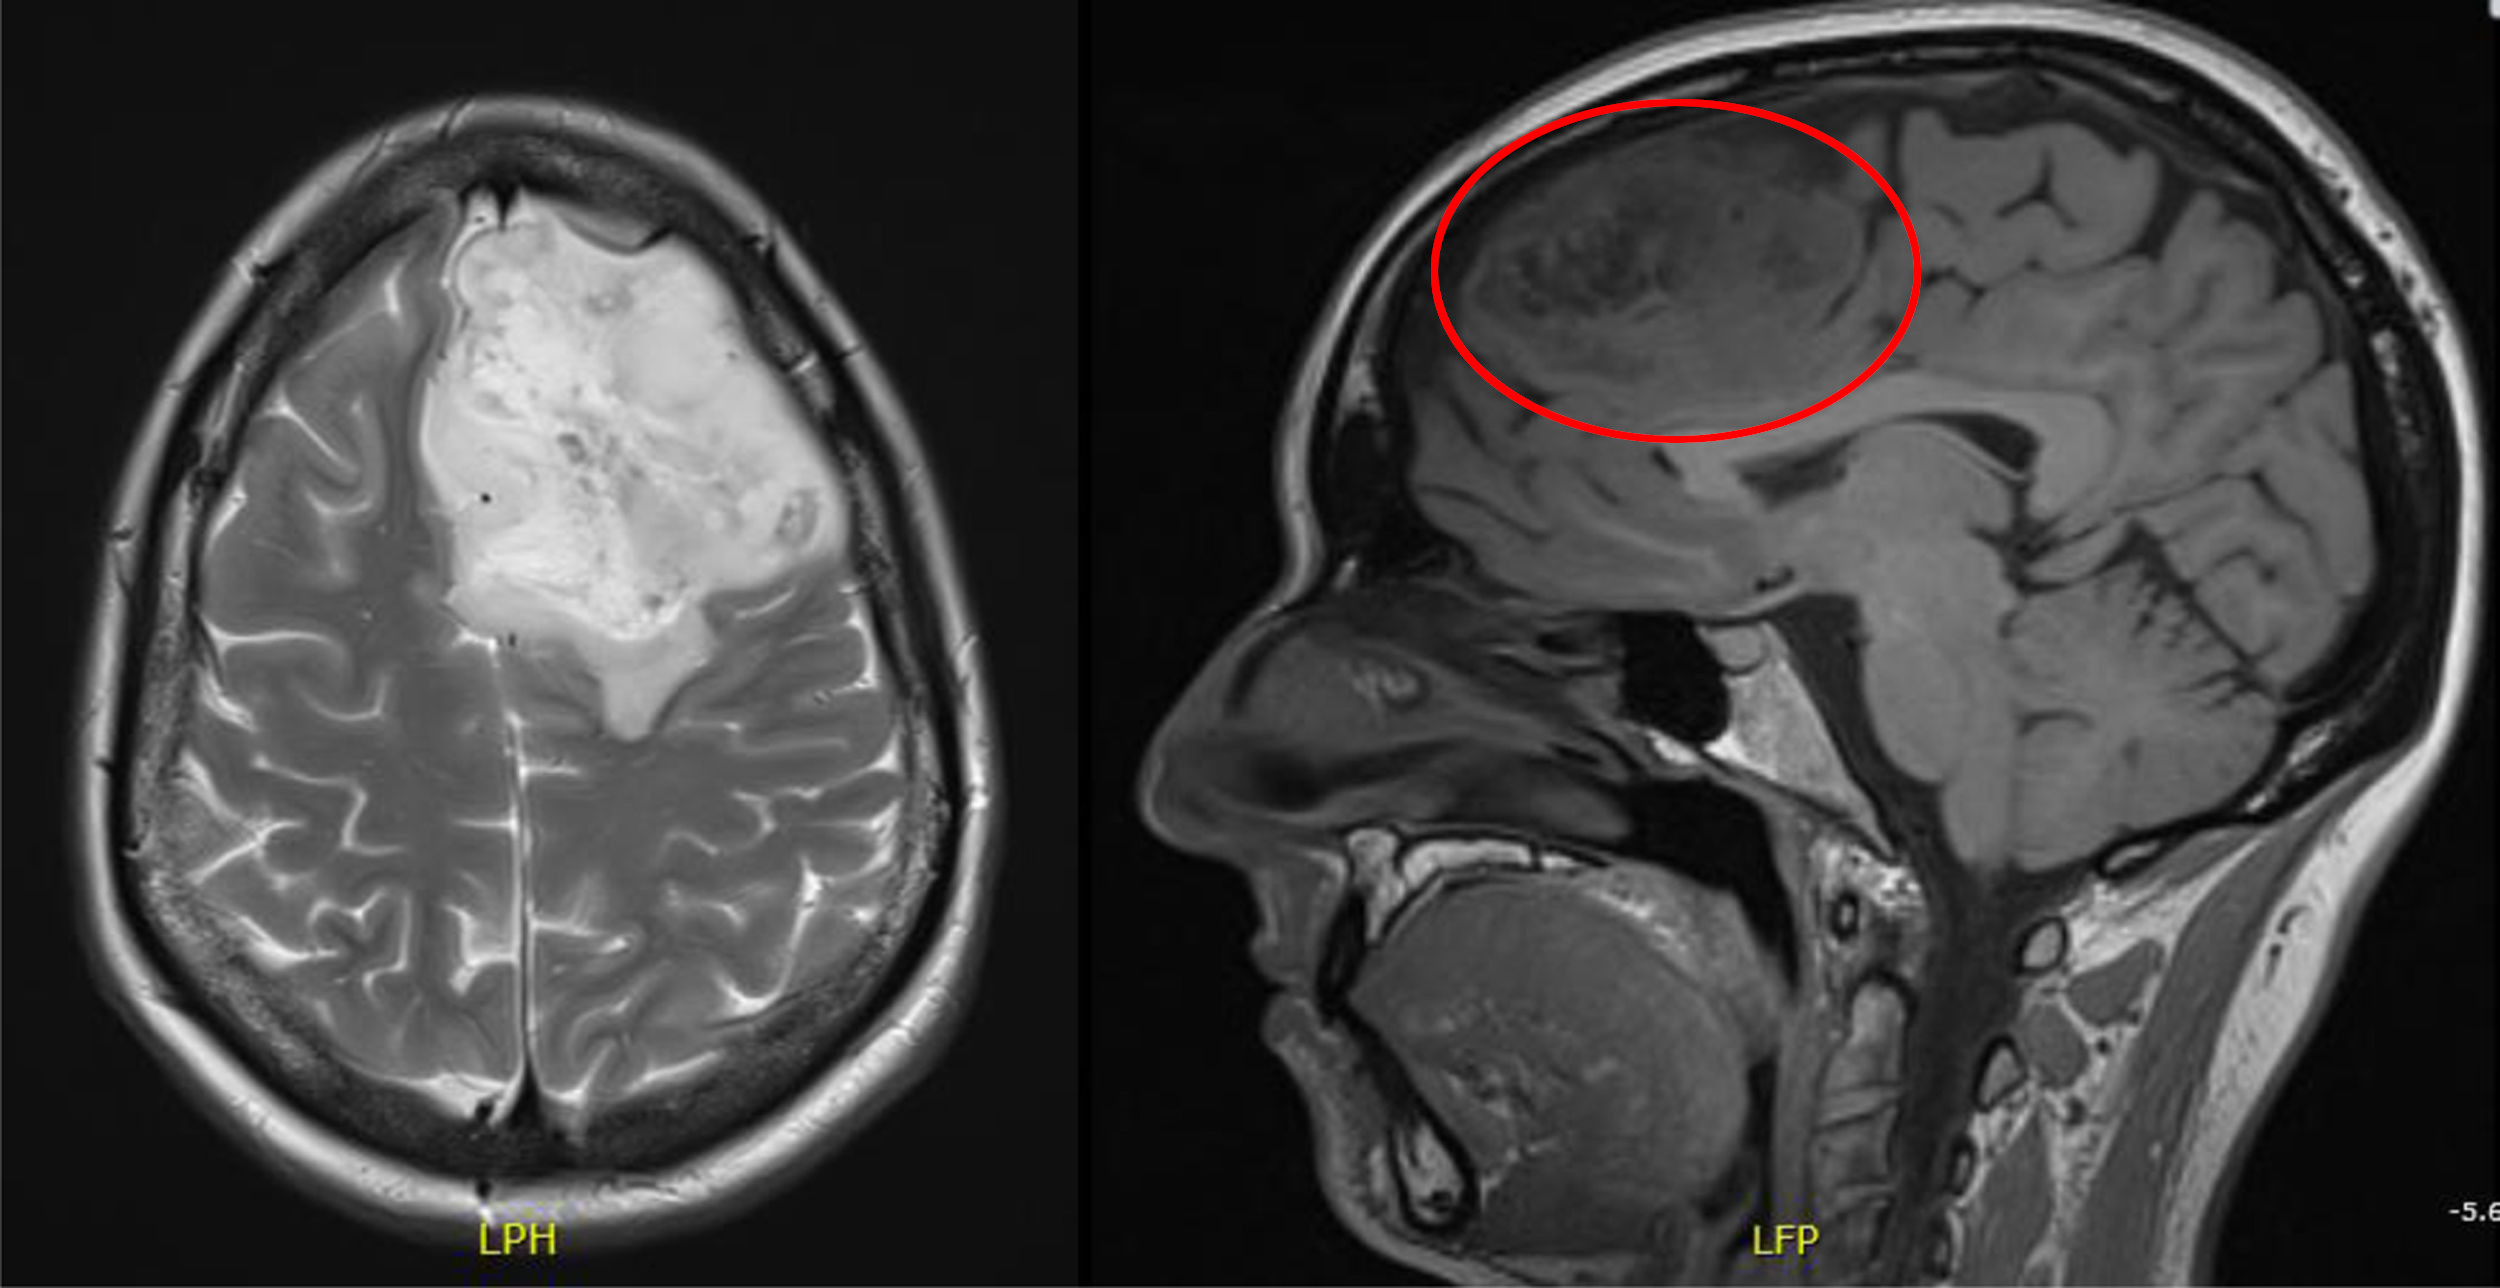

Astrocitoma

- Descrizione: Tumore del Sistema nervoso centrale, degli astrociti. Si localizza maggiormente nel cervelletto e nel cervello. In base al tipo può ricevere il nome di Astrocitoma di primo grado, anaplastico o glioblastoma multiforme.